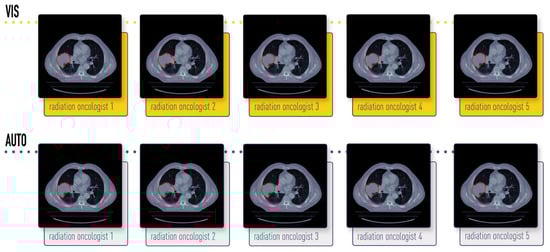

2.1. Dataset Description